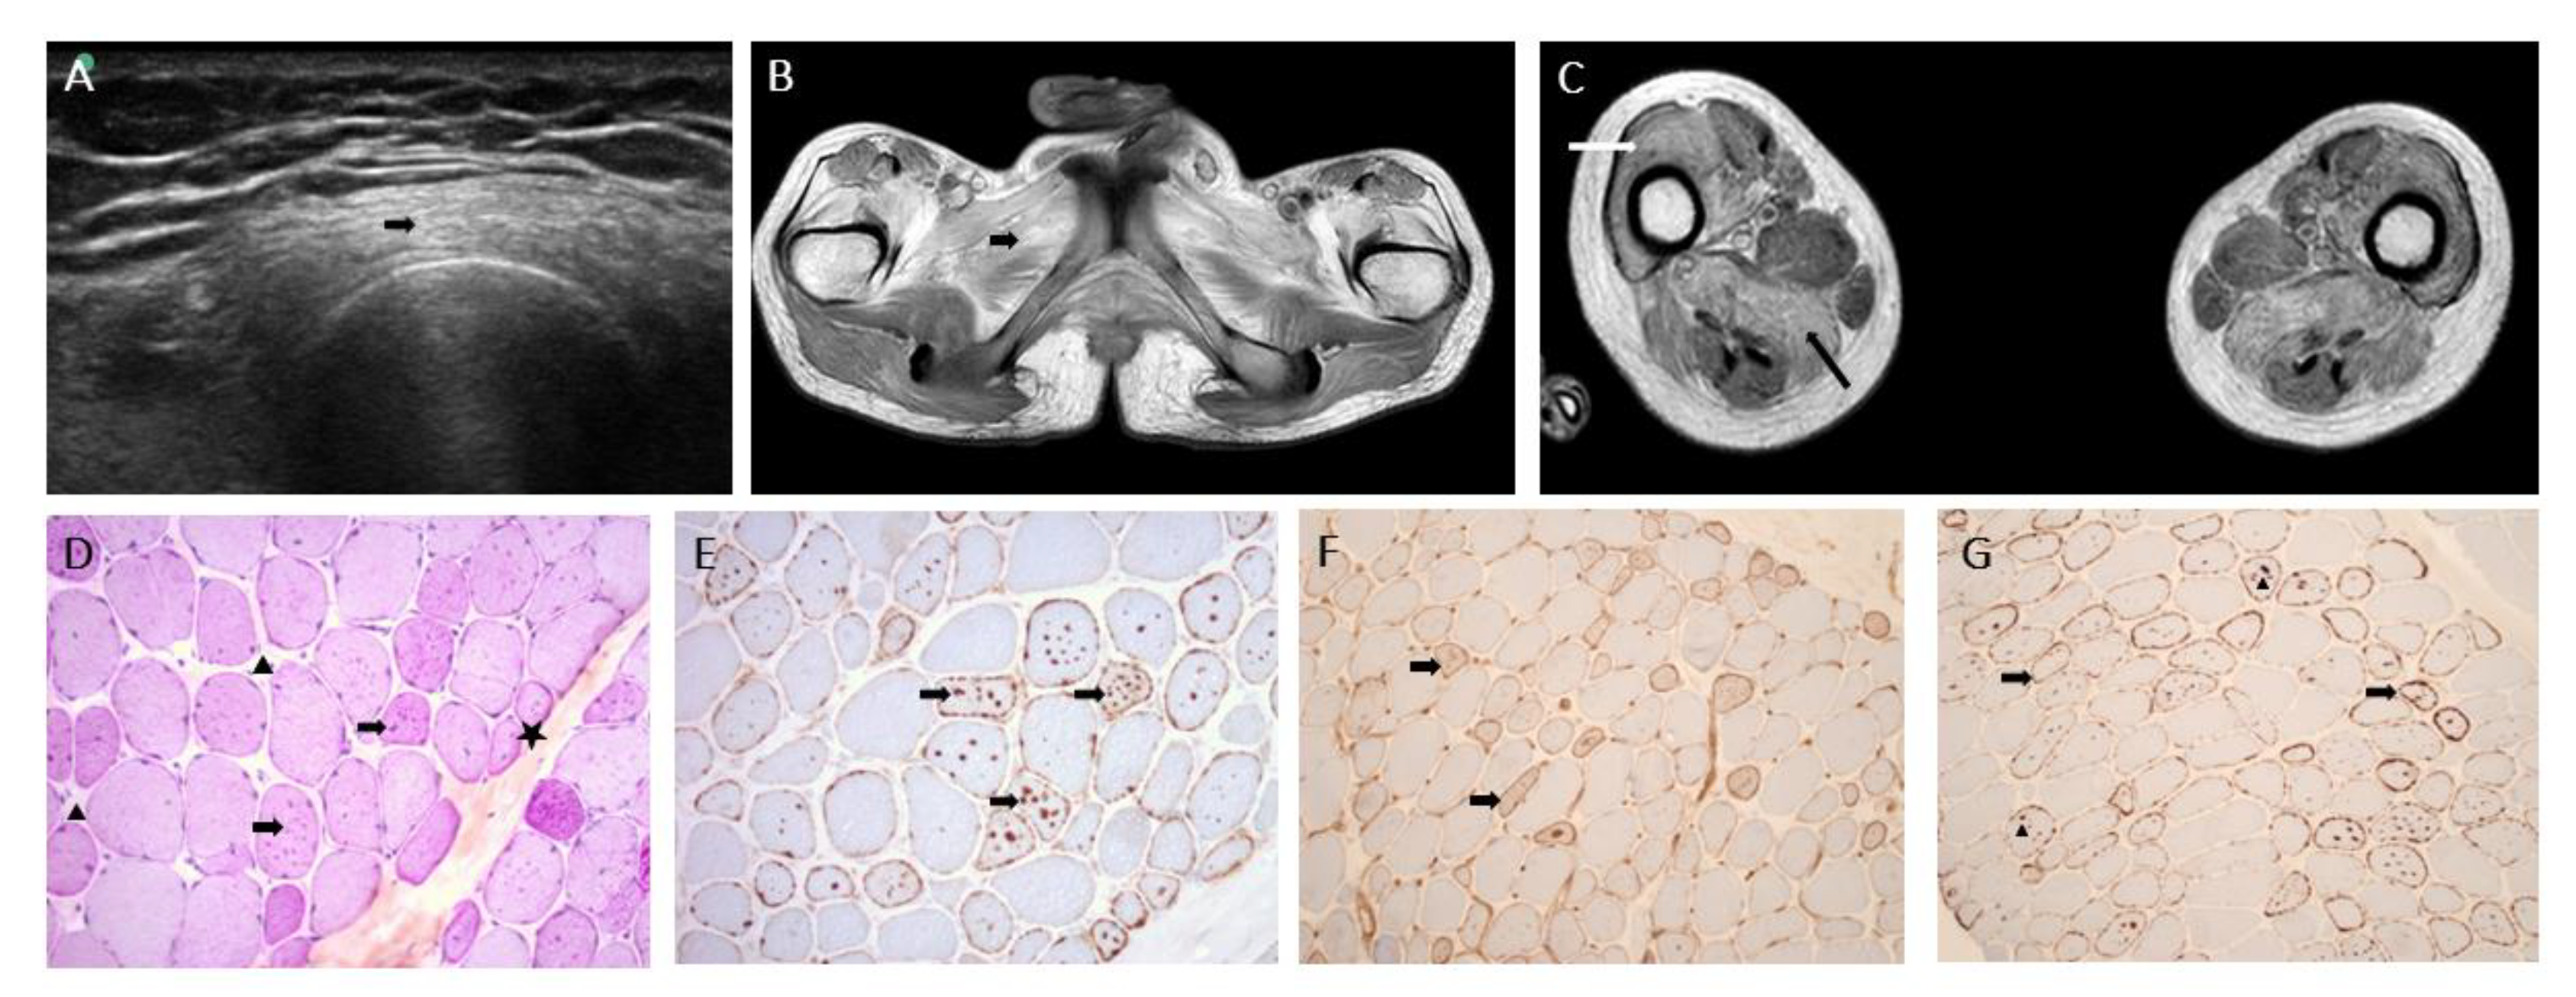

2.2. Muscle Biopsy